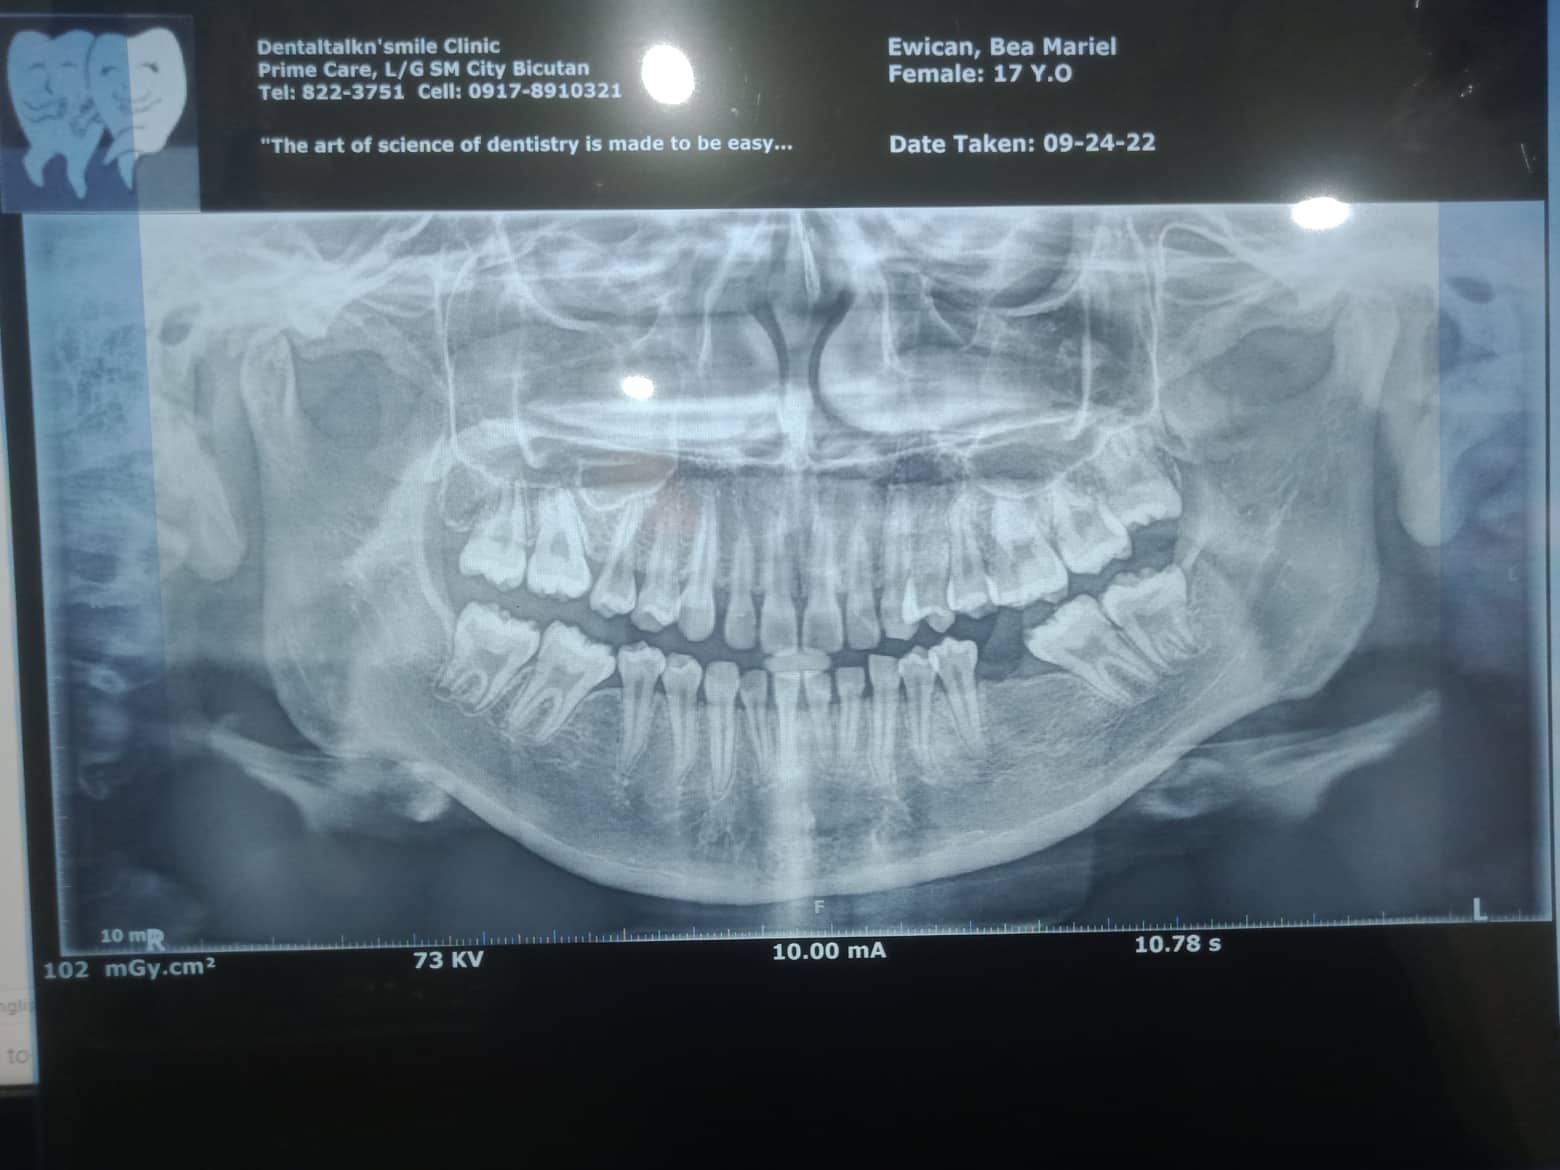

Edit Record Check our patient data records. Add patient information Patient Info Profile picture Last Name First Name Middle Name Birthdate Age Street Barangay City Country Zip Code Contact number Email Procedure 10/8/22- OP(L); RESTO #12 (MLABIAL), #11(MLINGUAL), #21(MLINGUAL) 1/21/23- Adj Same wire /23-UL same wire/reattached #15 04/1/23- Adj./Laser 07/01/23- 18niti upper/14 niti lower/laser- tmj pain relie 07/26/23- posterior splint reduction anterior 2mm posterior 3.5mm RX: procosa 08/12/23- 16SS L 18 NiTi U/ canine to canine Fox/ reduced splint to 0.5mm 09/20/23- 16ss UL 14- 16/ 24-26 chain 32 to 42 chain 10/18/23- closing space on lower Rw #42/ reduced height of splint same wire UL/ reattached #24 11/29/23-reattcahedment 24 reduced splint height box elastic anterior/ penguin same wire 01/05/24 ADJ same wire/ extrude 22/12 fox elastic extrusion 02/27/24 -same wire -reattachment #21,#41,#44 03/19/24 Adj 04/23/24 reattached #21 Adj 18 RC Niti-lower fox elastic(box) quadrant on posterior Occlusal pads on 46/37 installed same heights on the splint no more wearing of splint 06/11/24 ADJ same wire chain 12/22 reattached #42 08/30/24 adj class II elastic rabbit 5oz 12/21/24 class II elastic rabbit 3.5 oz chain U same wire next meeting close open bite reattached #33 01/30/25 Adj same wire reattached #33,42 box elastic penguin 04/01/25 Reattached #43, #42 Kobayashi wire #12,22 Class II elastic 5 oz. rabbit 06/13/25 same wire elastic chipmunk reattached #33 File 311406133_1205581633332847_2276520068966312254_n.jpg File 2 310788104_1189315538336441_931730254721665696_n.jpg File 3 bea_mariel_ewican.jpg File 4 bea_ewican.jpg File 5 File 6 File 7 File 8 File 9 File 10 File 11 File 12 File 13 File 14 File 15 File 16 File 17 File 18 File 19 File 20 Retain Record Retain Record Yes No Save Your Changes